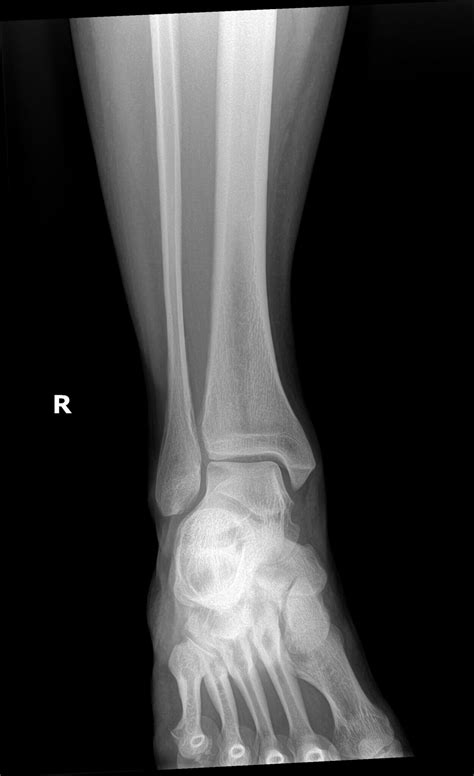

To substantiate the diagnosis, aesculapian pro rely on a combination of physical interrogation and diagnostic imaging. Because of the complexity of these crack, simple X-rays are much the start point, but they may not discover the entire extent of the bone translation.

Standard X-Ray Provides an initial view of the bone alinement and identifies obvious faulting.